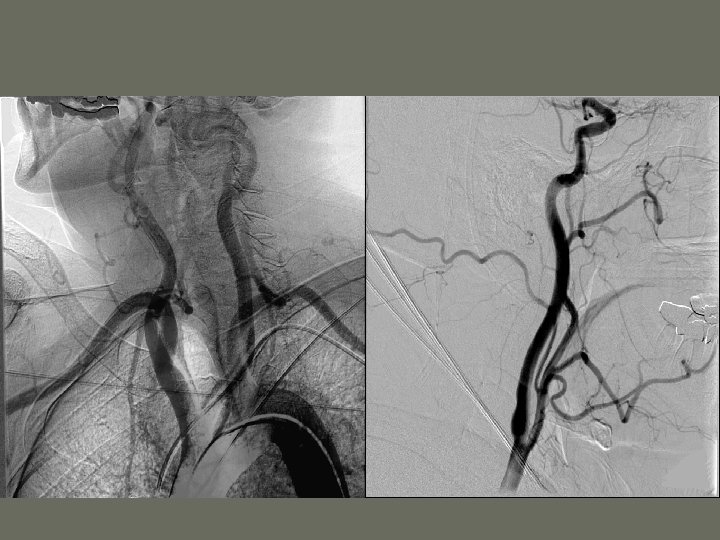

General Angiography Procedures 1. Cerebral Angiography • Vessels of the brain

General Angiography Procedures 4. Aortic Arch (Three Vessel Study) • demonstrates aortic arch and the three vessels that rise from it • _____ view (patient positioned or C-Arm angled) helps prevent superimposition of the vessels and open the aortic arch